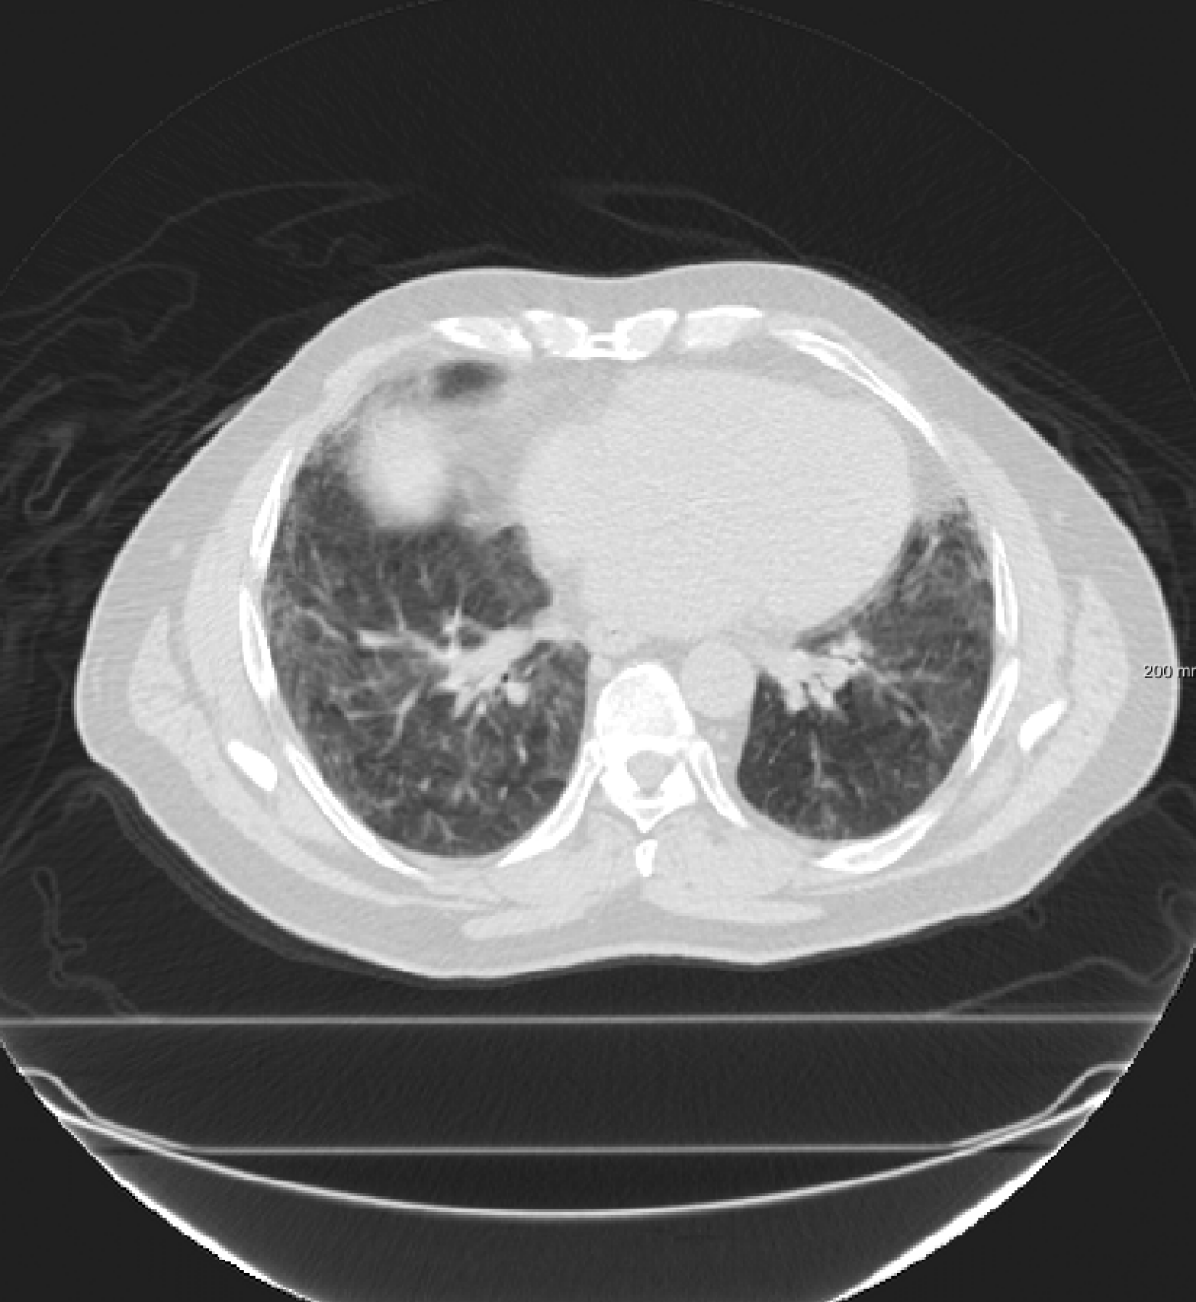

Three chest CT scan datasets are used in this study: The SPREAD (Stolk et al., 2007), the DIR-Lab-4DCT (Castillo et al., 2009) and the DIR-Lab-COPDgene dataset (Castillo et al., 2013).

In the SPREAD database, 21 pairs of 3D chest CT images are available with a baseline and a follow-up image in each pair. The follow-up images are taken after 30 months. Both images are acquired in the inhale phase. Patients in this study are aged between 49 and 78 years old. The size of the images is approximately with a mean voxel size of mm. About 100 well-distributed corresponding landmarks were previously selected (Staring et al., 2014) semi-automatically on distinctive locations (Murphy et al., 2011). Two cases (12 and 19) are excluded because of the high uncertainty in the landmarks annotation (Staring et al., 2014).

In the DIR-Lab-4DCT database ten cases are available. We use two phases of the available data: maximum inhalation and maximum exhalation. The size of the images is about with an average voxel size of mm.

For the DIR-Lab-4DCT database, a comparison between RegNet and affine, B-spline (three resolutions), an advanced conventional registration method using sliding motion (Berendsen et al., 2014) and three other CNN-based methods (Eppenhof and Pluim, 2018; de Vos et al., 2019; Sentker et al., 2018) is available in Table IV. It can be seen that training with “S+M” improved performance slightly with respect to just “S”. Adding the respiratory motion category improved performance substantially, as these are inhale-exhale pairs; this is predominantly caused by the patients where the TRE after affine registration was still quite large. An example visualization is also available in Fig. 5(f), showing that adding the respiratory motion category can align images better in the diaphragm region. The advanced conventional registration method that leverages sliding motion (Berendsen et al., 2014) is still better than RegNet. Note that RegNet was not trained on the DIR-Lab-4DCT data, similar to Eppenhof and Pluim (2018); Sentker et al. (2018). However, de Vos et al. (2019) and Eppenhof and Pluim (2018)-DIR methods were trained on the same database but using cross-validation to report the results. Also note that the results reported in Sentker et al. (2018) are averaged over all phases of DIR-Lab-4DCT (T00 to T10), while the results of other CNN methods (including RegNet) are reported between the maximum inhale and maximum exhale phase (T00 and T50). These reported results are therefore likely somewhat better than the results for T00 and T50 only.